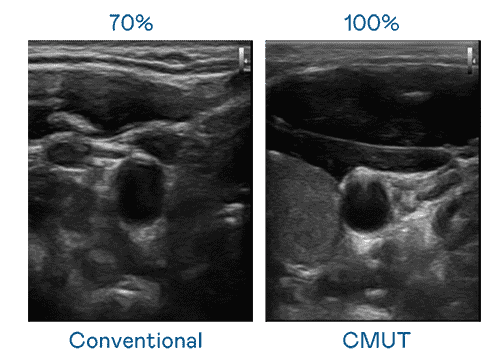

CMUT 技术是一种用电容式微机电元件来产生超音波讯号的技术。。。。与传统 PZT 压电式技术相比,,,CMUT 频宽增加 30%,,更宽频的超音波讯号让影像解析度大幅提升,,,,是实现高影像品质医疗超音波扫描、、、促进精准医疗发展的关键技术。。。

大频宽带来超清晰影像

超音波影像的解析度高低,,首先取决于探头能发出的讯号频宽。。。尊时凯龙 CMUT 可提供高清晰的超音波讯号,,提供高频宽、、、、高灵敏度、、影像纹理细节更高的超音波影像,,,,协助医护人员缩短影像判读时间及利用精准的医疗影像进行诊断。。。